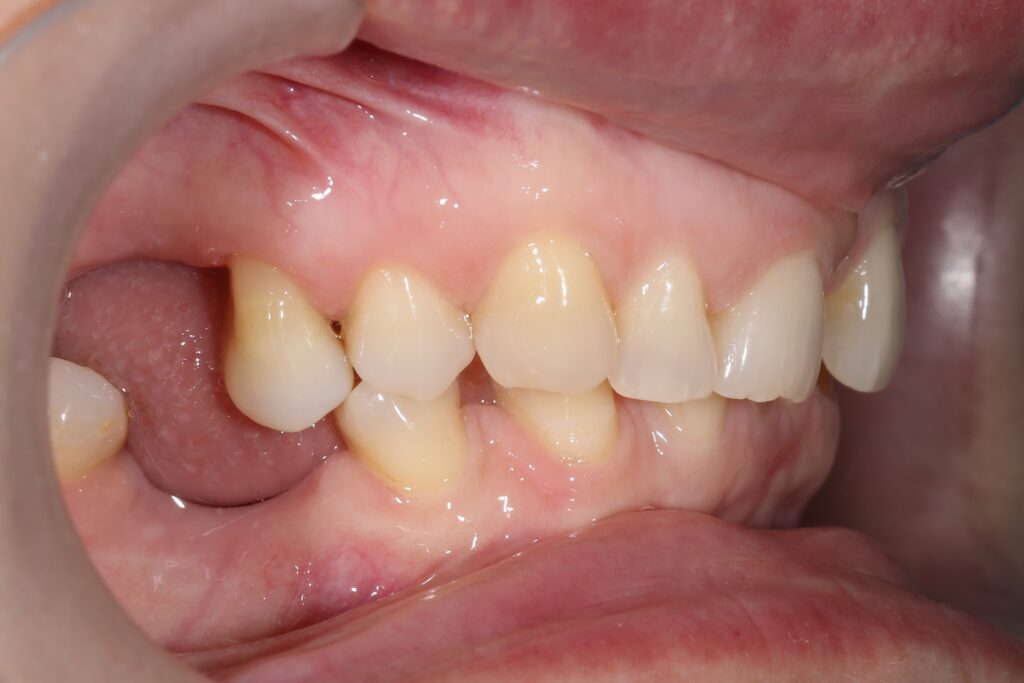

Ситуация до лечения

Пациентка 39 лет была направлена стоматологом-ортопедом для ортодонтической подготовки перед протезированием.

Из-за множественных давних удалений жевательных зубов, произошла деформация зубных рядов, зубы разъехались в область удаленных, что затрудняло протезирование в момент обращения к ортопеду.

Так же можно отметить сильное снижение высоты прикуса (верхние зубы на 100% перекрывали нижние, что вызывало хроническую травму десны), а также повышенную стираемость твердых тканей зубов,

что является следствием повышенной нагрузки, которую много лет испытывали передние зубы, в связи с отсутствием жевательных зубов.

пациент до брекетов